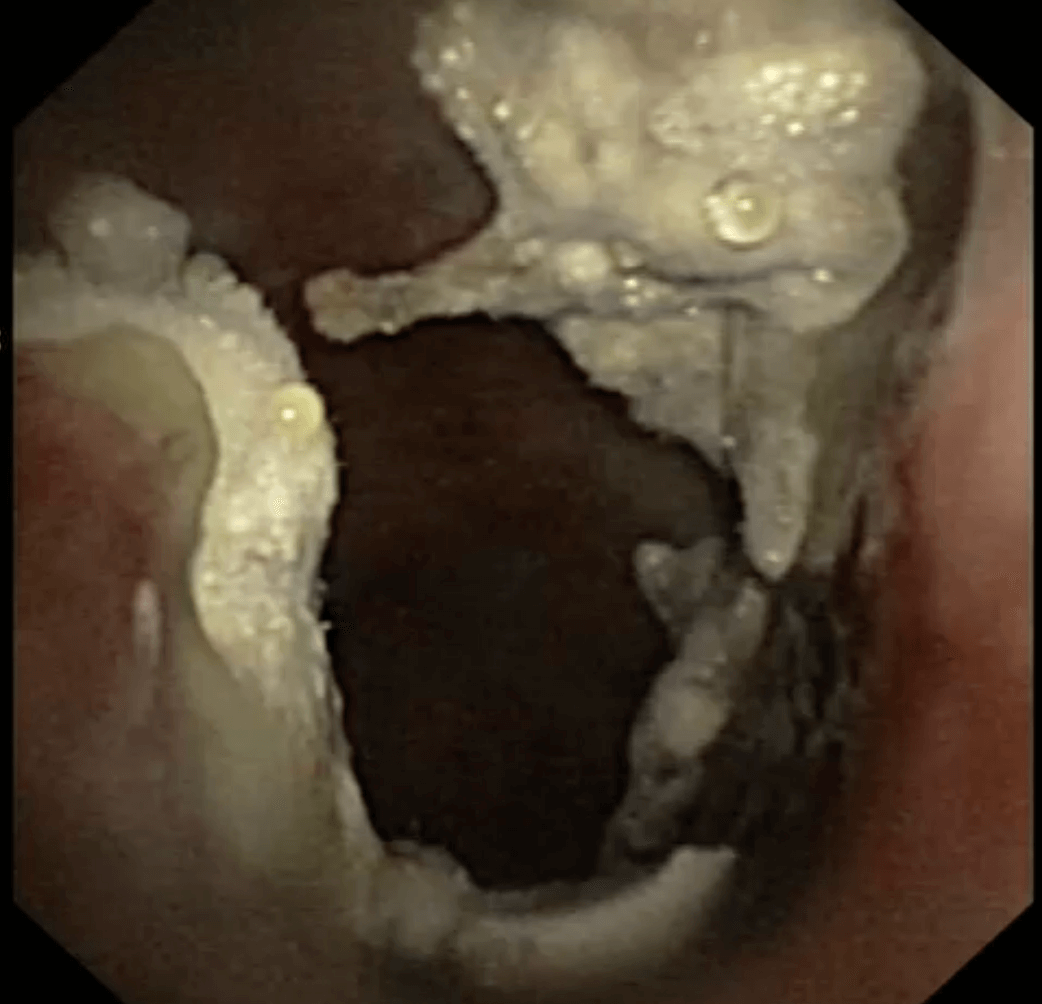

Plaques aspergillaires situées à l’entrée du sinus frontal, visualisées lors d’une rhinoscopie

Le scanner offre le meilleur moyen d'évaluer la destruction des tissus et d'examiner les sinus paranasaux. Les caractéristiques clés observées lors de la rhinoscopie comprennent une destruction des cornets nasaux et la présence de plaques fongiques blanches distinctes sur la muqueuse. La cytologie et/ou culture fongique des plaques observées durant la rhinoscopie permettent de confirmer le diagnostic.